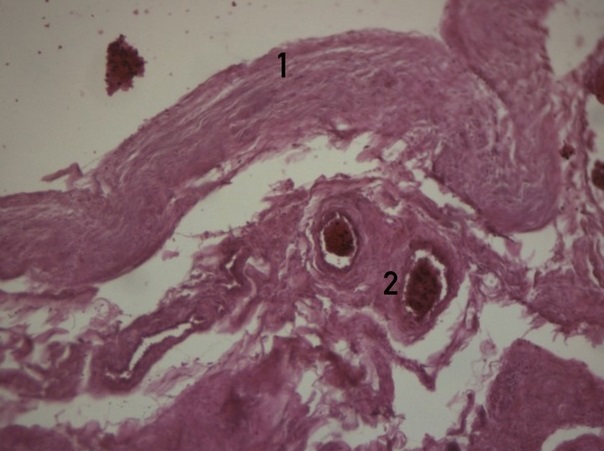

Рисунок 3 - Наботова киста шейки матки указана на рисунке цифрой 1

Примечание: окрашивание гематоксилином и эозином; увеличение х25

Рисунок 5 - Цервицит (указан на рисунке цифрой 1) с гидропической дистрофией эпителиальных и гладкомышечных клеток (указана цифрой 2)

Примечание: окрашивание гематоксилином и эозином; увеличение х25